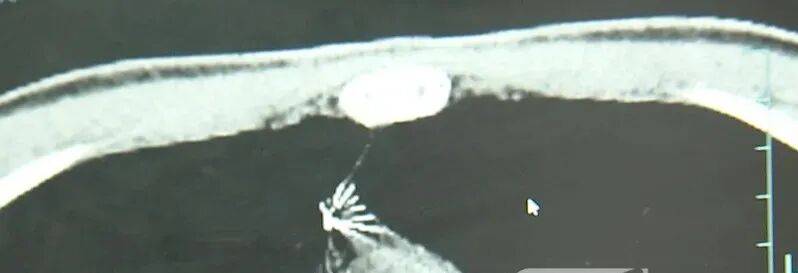

近日,安徽17岁小伙小陆参加征兵体检,胸片结果显示:胸腔内有一处金属高密度影,形态细长,像一根针。

进一步的CT检查确认,异物是一枚金属针,斜插在肺组织内,位置十分凶险。

杭州市第一人民医院心胸外科副主任冯兴说:“我们看到这个针的尖锐部,正好指向他体内的一个大血管,边上是上腔静脉和胸主动脉,因此这个针稍有不慎,就有可能造成周边血管的损伤,甚至危及生命。”

医生推测,那枚针很可能就是在那时候扎入体内的。针在小陆体内滞留了十几年,既没有引发感染,也没有造成气胸,堪称医学奇迹。上周四,医院为小陆实施了mini单孔胸腔镜微创手术,切口仅两厘米左右,成功将针完整取出。